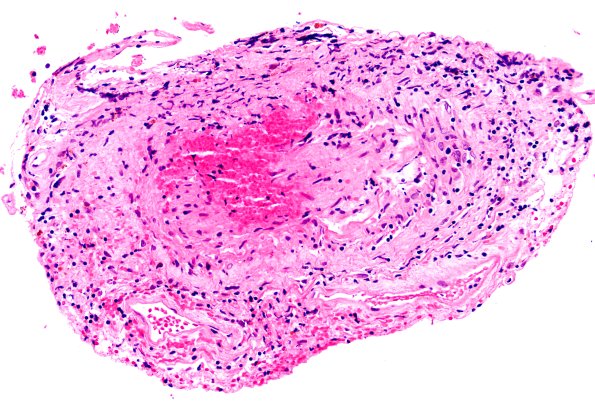

17B7 Vasculitis (Case 17) H&E 20x 4

17B7,8 There appear to be crumbs of nuclei in some foci of this arteriole consistent with a degree of angionecrosis. (H&E)